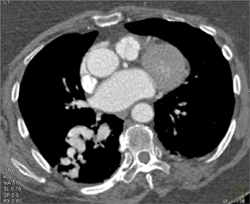

Clot in Aortic Arch